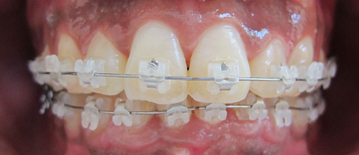

L’orthodontie vestibulaire esthétique

Un appareil multi-attache céramique est mis en place sur l’ensemble des dents.

L’utilisation d’attaches auto-ligaturantes en céramique n’entraine aucune coloration jaune inesthétique, ni aucun vieillissement dans le temps.

L’aspect des attaches reste donc inchangé tout au long du traitement.

L’adaptation dure en moyenne une à deux semaines.

Dans les cas de parodonte réduit où l’hygiène va être un élément déterminant, on préfère poser les attaches ( ou bagues) sur la face visible des dents c’est à dire en vestibulaire pour faciliter le passage de la brosse à dent et des brossettes avec un bon contrôle visuel.

La durée moyenne d’un traitement multi-attache vestibulaire varie de 6 mois à 30 mois.

Les rendez-vous sont espacés de 4 à 8 semaines.

Le temps passé au fauteuil est court.